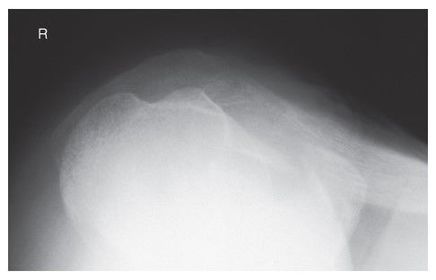

Which projection/position is this? Transthoracic Shoulder ___________________ ribs are blurred out from orthostatic breathing